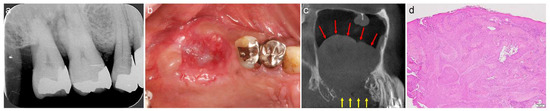

A 58-year-old male was referred to our clinic by his dentist for implant treatment of the right maxilla in 2018. Well-defined, faintly radiopaque antral lesions were observed on the mesiodistal section of the CT image acquired at the first visit. Moreover, marked alveolar bone resorption was observed in the regions surrounding 16, 15, and 14 (Figure 1a, red arrows). The requirement for extraction of these teeth and sinus floor elevation for implant treatment was explained to the patient. The well-defined, faintly radiopaque antral lesions were found to have disappeared on the CT image acquired 3 months after the extractions (Figure 1b); thus, sinus floor elevation was performed using β-TCP granules (Osferion; Olympus Terumo Biomaterials, Tokyo, Japan) alone and 17 was extracted simultaneously at our clinic. CT images acquired 6 months postoperatively revealed a radiopaque area at the site that underwent sinus floor elevation. Swelling of the sinus membrane was not observed (Figure 1c).

Figure 1.

The mesiodistal section of CT images of the right maxillary sinus. (a) Antral, well-defined, faintly radiopaque lesions (red arrows) and marked alveolar bone resorption are observed near 16, 15, and 14. (b) The well-defined, faintly radiopaque antral lesions disappeared 3 months after extraction. (c) A radiopaque area is observed at the sinus floor elevation without swelling of the sinus membrane six months postoperatively.

A 44-year-old female scheduled to undergo implant placement for the replacement of 27 was referred to our clinic in 2014 for sinus floor elevation owing to insufficient bone height. A well-defined, faintly radiopaque antral lesion was observed on the mesiodistal section of the CT image acquired at the first visit (Figure 2a, red arrows). A periapical lesion was observed at the palatal root apex of 26, indicating periapical disease (Figure 2a, yellow arrow); consequently, the tooth was extracted by the original dentist. The antral radiopaque lesion had disappeared almost completely four months after the extraction (Figure 2b). Thus, sinus floor elevation was performed using β-TCP granules alone at our clinic. CT image acquired nine months postoperatively revealed a radiopaque area at the site where sinus floor elevation was performed without swelling of the sinus membrane (Figure 2c).

Figure 2.

The mesiodistal section of CT images of the left maxillary sinus. (a) Well-defined, faintly radiopaque antral lesions (red arrows) and bone resorption at the palatal root apex of 26 (yellow arrow) are observed. (b) Almost all well-defined, faintly radiopaque antral lesions had disappeared four months after the extraction. (c) A radiopaque area is observed at the sinus floor elevation without swelling of the sinus membrane nine months postoperatively.